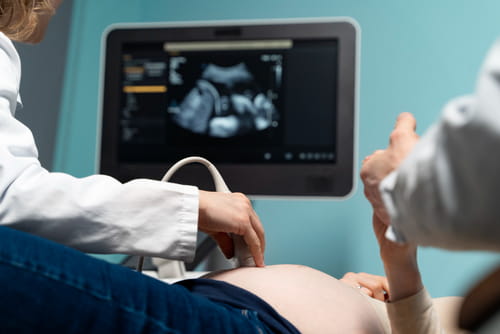

Ecografías del embarazo

Precisión médica y tecnología de avanzada para acompañar cada etapa del embarazo y cuidar lo más importante: tu bebé.